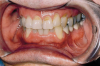

Fig 3. A clinical example of severe chronic endogenous biocorrosion effects from anorexia nervosa. This patient was diagnosed and treated by a physician for this condition, which left lingual maxillary enamel almost free of this hard tissue. (Photograph is courtesy of Ali Tunkiwala, MDS, used with his permission.)

Figure 3